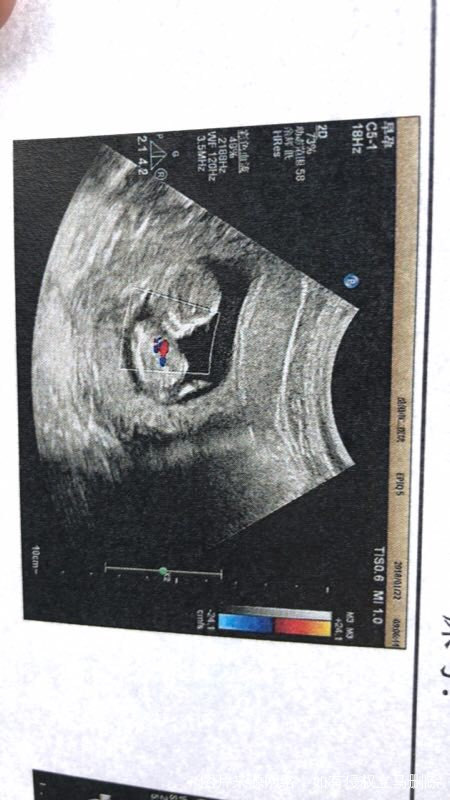

跟我老公认识六年了,没有生小孩,觉得挺对不起他的,就去医院检查,输卵管伞端积水……今年7月份果断做把输卵管结扎了,8月份取长沙中信湘雅准备试管之路……去的时候刚好来了月经第二天,做了试管前的检查~然后医生给我定了方案,长效长,10月份开始进周打了一针降调然后回家,11月3号去医院开始促排打针~打了13天,然后夜针,取卵,20号。终于等到那天听结果,紧张的要命,配了4个胚胎,2个8等级的,2个5等级的,医生说今天2个8的,2个5拿去养囊,成了两个4bc的囊胚,冻起来了……14天后也就是12月3号取医院抽血,成功了~非常感谢🙏中信湘雅,也很庆幸自己当时的决定要去试管~现在宝宝14周了~三个多月了~只希望宝宝健健康康平平安安的出生,爸爸妈妈爱你😘。下面附上一张我们家宝贝的b超照片